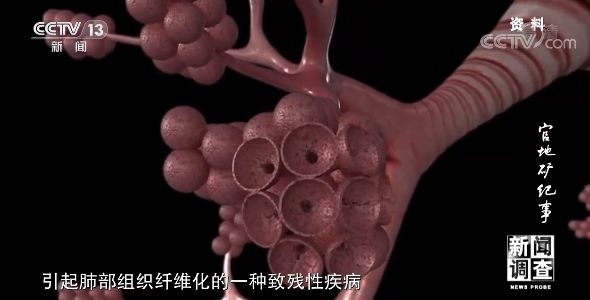

煤矿职工在煤炭生产过程中会接触到粉尘、噪声等职业危害因素,对健康和生命构成威胁。尘肺病是矿工最常见的职业病,由于患病率高、难以治愈等特点,一段时间以来,尘肺病问题得到了国家和社会的广泛关注。

由于行业粉尘特点和历史上防尘技术落后等原因,采掘一线的煤矿工人长期面临着粉尘的危害和尘肺病的折磨。

尘肺病是粉尘通过呼吸进入肺部、引起肺部组织纤维化的一种致残性疾病,它会导致呼吸系统感染,出现胸痛、呼吸困难等一系列症状,此外,还会引起多种并发症,甚至因呼吸衰竭导致死亡。

西山煤电总医院职业病科主任 田红霞:口唇的紫干,运动能力耐力的下降,另外的话可能还会引起来心脏的并发症,肺心病、肺气肿这些,再严重的话可能还会引起大脑的缺氧,其实它是一个全身的疾病,它能引起全身各个系统缺氧的这种表现。

除了吸氧之外,医院还有输液抗感染、机械震动排痰、肺灌洗等治疗手段。但令人遗憾的是,目前尘肺病依然是一种在临床上无法治愈的疾病。

西山煤电总医院职业病科主任 田红霞:吞噬细胞对粉尘吞噬之后形成一些结节,最后形成大块的结节的表现,这就叫纤维化。现在肺纤维化的逆转在世界上也是一个难题,没有很好的办法。完全逆转的可能性目前是没有的,只能说是延缓它的进一步发展。而我们其实做的是一些亡羊补牢的工作,已经得了尘肺病那我们怎么让患者延长生命,减轻他的痛苦,提高生活质量。所以说我们时候就强调防护预防重于治疗,其实就在这一点上,因为它没有办法彻底根治。